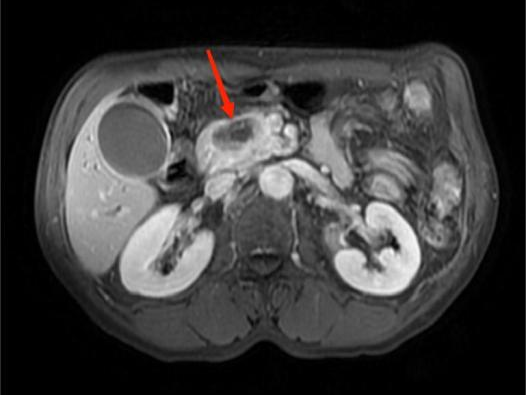

图4A

图4B

图4C

图4D

典型病例4:

男性,59岁,间断左中上腹部疼痛2个月,为隐痛,程度较轻,伴夜间痛。图A:T1WI示胰腺体部见团片状稍低信号影,边界不清。图B:增强扫描示病灶呈弱强化。图C:胰腺体尾部实质萎缩。图D:MRCP示远端胰管扩张。